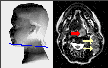

Shown above is a pre-treatment MRI image of a 50-year-old female with a poorly differentiated T2N2 squamous cell carcinoma of the base of the tongue. The MRI reveals both the primary tumor and the involvement of two left cervical lymph nodes.

Now examine the corresponding pre-treatment FDG-PET image for this patient. The intense metabolic activity of the tumor and the involvement of cervical nodes is readily apparent in the FDG-PET image. The extent of the tumor can be gauged by examining the cinematic set of FDG-PET scans on the left, although this would also be apparent in the complete set of MRI images.

At 6 weeks following radiation treatment, the patient had a persistent 2 cm left neck mass on physical exam, and the MRI scan showed persistent adenopathy (red arrow) and post-radiation changes in the oropharynx with the primary tumor being no longer visible. The FDG-PET scan shows a marked resolution of tumor activity in both the primary tumor and lymph nodes. Fine needle aspirate of the cervical mass was non-diagnostic. This mass gradually decreased in size on physical examination, and the patient has continued to do well clinically.